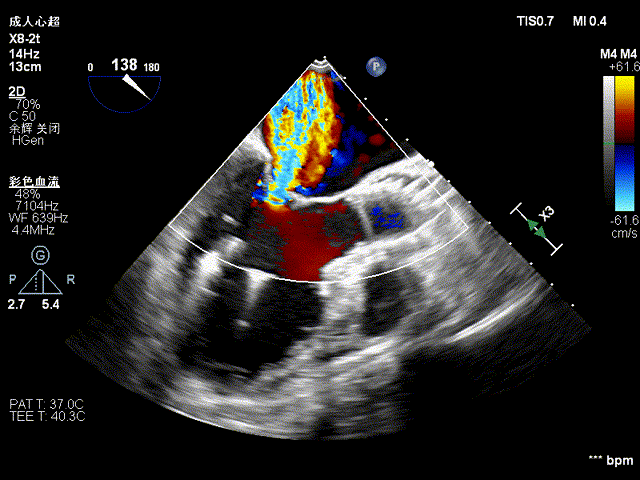

瓣膜快速释放到位后TEE观察患者二尖瓣反流明显减少,左心室收缩功能得到改善,心电监护提示ST段逐渐恢复至正常,心率下降至80次/分,血氧饱和度升至98%,血压逐渐上升到正常,血流动力学趋于稳定。造影观察瓣膜形态、位置良好,无瓣周漏。术后当天拔除气管插管,第二天患者即可下床活动。

释放后即刻评估

观察20min后再评估

目前中南医院TAVR术中多模态影像技术协同指导,术中“超声语言”与“DSA语言”协同,及“以解剖为中心”和“以影像为中心”两种语言的统一(例如超声常用三腔心切面对应为DSA下的RAO+CAU投照角度),可在手术过程中可快速、及时评判并发症、导丝导管的位置等;帮助假体瓣膜更快更直接的定位;术中即刻评估,协助医生快速判断植入的效果,如瓣膜的植入深度与毗邻组织的关系,瓣膜的形态、瓣周漏评估等。